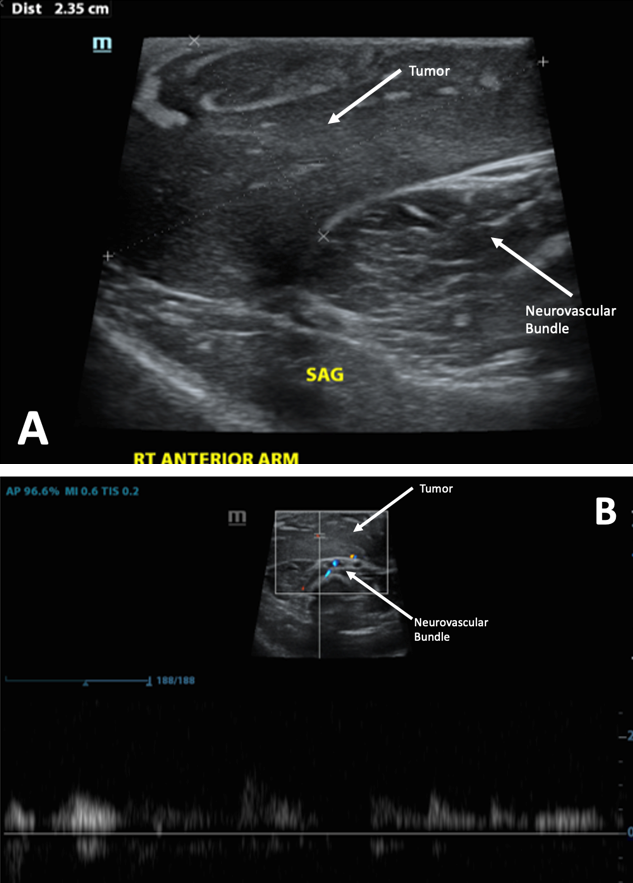

The family electively presented to a multidisciplinary vascular anomalies clinic for a second opinion and requested to confirm the diagnosis with a biopsy. At this time, clinical examination showed a 5 × 4-cm soft mass within the subcutaneous tissue that extended from the medial shoulder to distal upper arm within the bicipital groove. There was minimal skin discoloration, the mass was nonpulsatile and nontender, and there were no functional deficits (Figure 1B). An ultrasound was repeated that showed a well-circumscribed mass in the anterior compartment of the right upper arm with a predominantly hypoechoic signature and internal echogenic striations (Figure 2A). Doppler ultrasound demonstrated arterial waveforms within the mass (Figure 2B). A core biopsy was performed by interventional radiology, which demonstrated giant cell fibroblastoma (GCF) morphology. Subsequent magnetic resonance imaging (MRI) showed a 7.8 × 4.6 × 5.3-cm well-circumscribed subcutaneous mass with myxoid nodular and interstitial fibrous elements (Figure 3A). The mass showed variable enhancement (Figure 3B and 3C) and was above the neurovascular structures and muscle fascia (Figure 3C).

Figure 2. Ultrasound images. (A) Gray scale ultrasound demonstrates circumscribed mass in the anterior compartment of the right upper arm with a predominantly hypoechoic signature and internal echogenic striations. (B) Doppler ultrasound demonstrates arterial waveforms within mass.